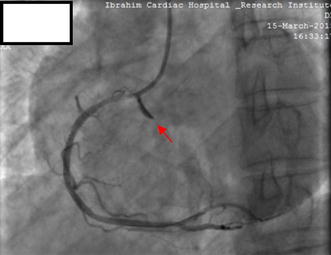

Following CAG, he was selected for angioplasty of the RCA. The RCA was easily cannulated with a soft tipped 6-French JR 3.5 guiding catheter (USA). After the selection of the guiding catheter in the RCA, a 0.014 in. Asahi Sion Blue PTCA guide wire (Asahi Intecc Co., Ltd., Japan) was advanced to cross the lesion. Pre-dilatation was done by 2.5 × 15 mm Sapphire balloon at an inflation pressure of 12 atmospheres (ATM) for 10 s. Stenting was done by 2.75 × 38 mm novolimus-eluting DESyne stent (Elixir medical corporation, Sunyvale, CA) at 16 ATM for 20 s, with restoration of thrombolysis in myocardial infarction (TIMI) III flow. At this point we observed an Ellis type II perforation in the ostial RCA, as evidenced by subtle contrast (Fig. 2; Additional file 1: Video S1). The next contrast injection given very gently showed that the perforation had extended into the right coronary sinus of Valsalva, as evidenced by contrast dye beyond the RCA ostium and retrograde stasis limited to the sinus of Valsalva (Fig. 3; Additional file 2: Video S2). There was no rupture of the balloon. Despite coronary perforation, the patient remained haemodynamically stable, reported no chest discomfort and electrocardiogram showed no sign of new ischemia. Urgent cath lab TTE showed no pericardial effusion or aortic regurgitation (AR). Serum cardiac enzymes and troponin I were within normal range.

Fig. 3.

Coronary angiography following the next contrast injection showing extension of RCA perforation into the right coronary sinus of Valsalva (red arrow)